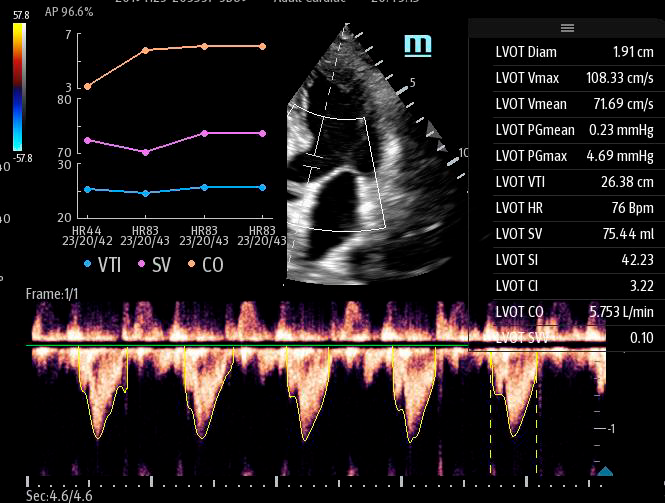

Автоматическая оценка потока выносящего тракта – Smart VTI

Чтобы использовать уравнение, нужно получить поток выносящего тракта левого желудочка в PW допплере — это достаточно кропотливая работа. В ультразвуковых системах Mindray Resona i9 эта задача решается автоматической оценкой потока выносящего тракта – Smart VTI.

Доктору остается получить 5-ти камерное сечение сердца и нажать одну кнопку на сенсорном экране. Прибор сам выберет расположение контрольного объема, получит спектрограмму и обведет спектр с расчётом всех показателей. Быстро и эффективно.